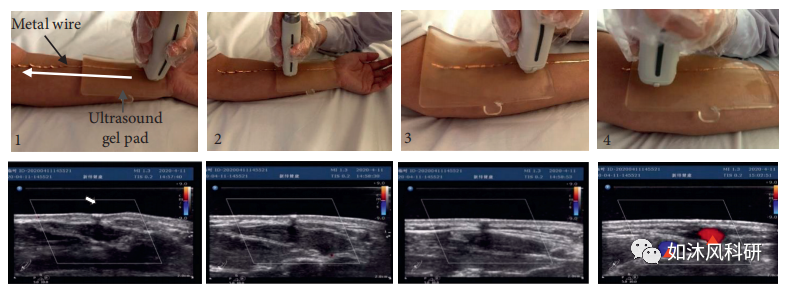

8.荧光谱线的横向超声成像